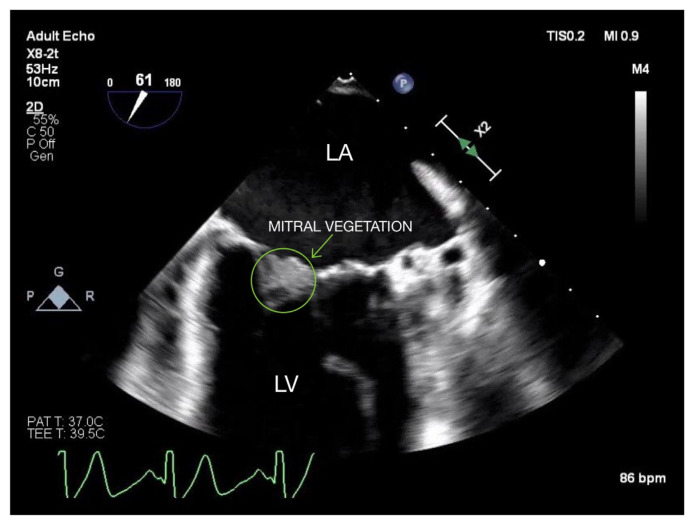

Abstract Image